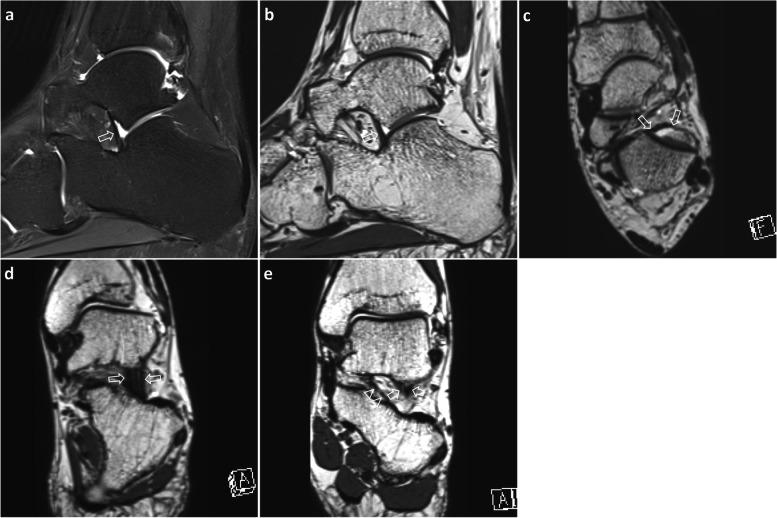

Only the 2D sequences interpreted by two readers showed a sensitivity of 64.0-96.0%, a specificity of 29.6-44.4%, a positive predictive value of 51.6-56.4%, and a negative predictive value of 57.1-88.9%. Addition of isotropic 3D sequences changed the sensitivity to 60.0-80.0%, specificity to 63.0-77.8%, positive predictive value to 64.3-76.9%, and negative predictive value to 66.7-80.8%. The overall diagnostic performance of isotropic 3D sequences (AUC values: 0.679-0.816) was higher than that of 2D sequences (AUC values: 0.568-0.647). Inter-observer and intra-observer agreement between the two readers was moderate-to-good for both 2D and 3D sequences. The diagnostic accuracy in 19 patients with tarsal sinus fat obliteration tended to increase from 26.3-42.1% to 57.9-73.7% with isotropic 3D sequences compared with 2D sequences.

Isotropic 3D MRI was feasible for the assessment of IOLV tear prior to subtalar arthroscopy. Additional 3D sequences showed higher diagnostic accuracy compared with conventional 2D sequences in IOLV evaluation. Isotropic 3D sequences may be more valuable in detecting IOLV tear in case of tarsal sinus fat obliteration.